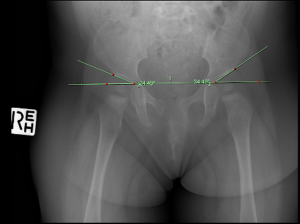

At 9 months 29 days of age (8M29D), an A-P lumbopelvic x-ray was arranged by a GP. This revealed a right acetabular angle of 24 degrees, but a left acetabular angle of 34.5° degrees. A clear disruption to Shenton’s line signifying left acetabular dysplasia was also apparent. A private pediatric orthopedic consultation resulted in the recommendation of rhino bracing for 23 hours per day for a period of 12 weeks. The parents were advised that there may be difficulty with tolerating the brace, and due to a rash appearing after one week, Denis Browne bar bracing was utilized during naps and night-time in conjunction with the rhino brace.

Figure 1: X-ray at 8M29D Showing Acetabular Angles Prior to Bracing

Figure 1 shows a right acetabular angle measure of 24.49° and a left of 34.49°. Repeat x-ray at 12 months of age (12M8D) showed a one-degree improvement in left acetabular angle to 33 degrees, with the right acetabular angle not measured. The pediatric orthopedic specialist recommended a further 12 weeks of bracing at 23 hours per day. Due to the poor response to bracing and compliance issues, the parents at this point ceased bracing.